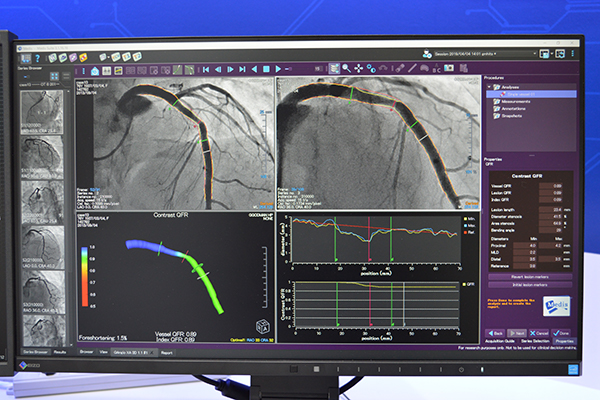

学術研究用として提供される3D心血管アンギオ画像解析システムの「QAngio XA 3D」(オランダMedis medical imaging systems)は,2016年の国内発売以降,導入施設数を伸ばしている。安定冠動脈疾患に対する虚血の機能評価“QFR(Quantitative Flow Ratio)解析”(オプション)が可能で,ブースでは「オンラインQFRの診断性能FAVOR II EUROPE-JAPAN試験」(J. Am. Heart Assoc., 2018.)の結果を紹介した。

QAngio XA 3Dは,統合型血管解析システム「QAngio XA」のアルゴリズムが踏襲されている。3D QCAでは,2方向の血管造影画像から3D再構成を行うことで,狭窄率や病変長を計測できる。

QFR解析は,3D再構成した血管像から独自のアルゴリズムによってQFRを算出。算出された値は,血管像にカラー表示することで直感的な観察が可能で,多方向からの確認もマウス操作のみで行うことができる。QFRには,far distalのQFR“Vessel QFR”,任意の指定範囲のQFR“Lesion QFR”,任意の指定位置のQFR“Index QFR”の3種のパラメータがある。

「QAngio XA 3D」はオプションで“QFR解析”を提供